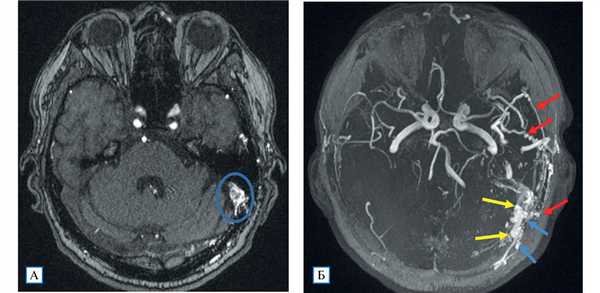

Проведенное дуплексное сканирование сосудов головы обнаружило признаки артериовенозной мальформации в бассейне левой наружной сонной артерии с артериализацией и усилением кровотока по внутренней яремной вене. Усиление скорости кровотока по задней околоушной артерии позволило предположить ее в качестве «питающего» сосуда (рис. 1). Контрастная МР-ангиография подтвердила наличие артериовенозного соустья с вовлечением поперечного и частично сигмовидного синусов слева (рис. 2).

Рис. 2. МР-ангиография (3D TOF-ангиография)

Примечание. А — сброс крови из ветвей наружной сонной артерии в левый поперечный синус; Б — аксиальная MIP-реконструкция: визуализируются нормальные артерии Виллизиева круга; слева расширенные и извитые ветви наружной сонной артерии (алые стрелки), из которых происходит сброс крови в поперечный и сигмовидный синусы (желтые стрелки), извитость и расширение дуральных вен вследствие полнокровия (голубые стрелки).